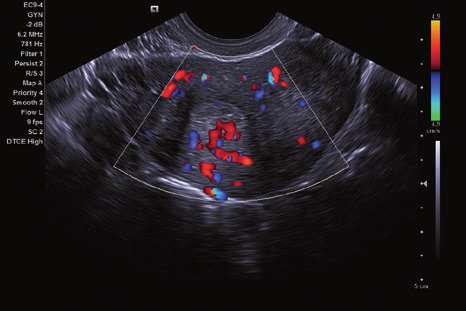

Das ACUSON NX2 Ultraschallsystem besitzt eine zukunftsfähige digitale Plattform mit nahezu unerreichter Bildqualität und sorgt für effiziente und zuverlässige Diagnosedaten. Die Vielseitigkeit des Ultraschallsystems wird mit einem großen kompatiblen Portfolio an Schallköpfen gedeckt, und so ist für jeden Anwendungsbereich etwas dabei. Die Bedienkonsole ist intuitiv aufgebaut und optimiert und erlaubt bis zu vier nach vorne gerichteten Schallkopfanschlüssen für eine enorme Effizienz und schnellen Workflow. So lassen sich bei der fetalen Bildgebung außergewöhnlich detailgetreue Darstellungen des Fetus im Gesicht zeigen oder durch die herausragende Farbdopplersensitivität bei der Darstellung der kleinen Gefäße des zystischen Schilddrüsenknotens kleinste Details erkennen. Weiterhin besticht das NX2 mit einfacher Aufrüstbarkeit bei wachsenden Anforderungen für Ihre zukünftigen Anwendungen und kompatible skalierbare Schallköpfe verringern ihren Kapitaleinsatz um bis zu 31 %.